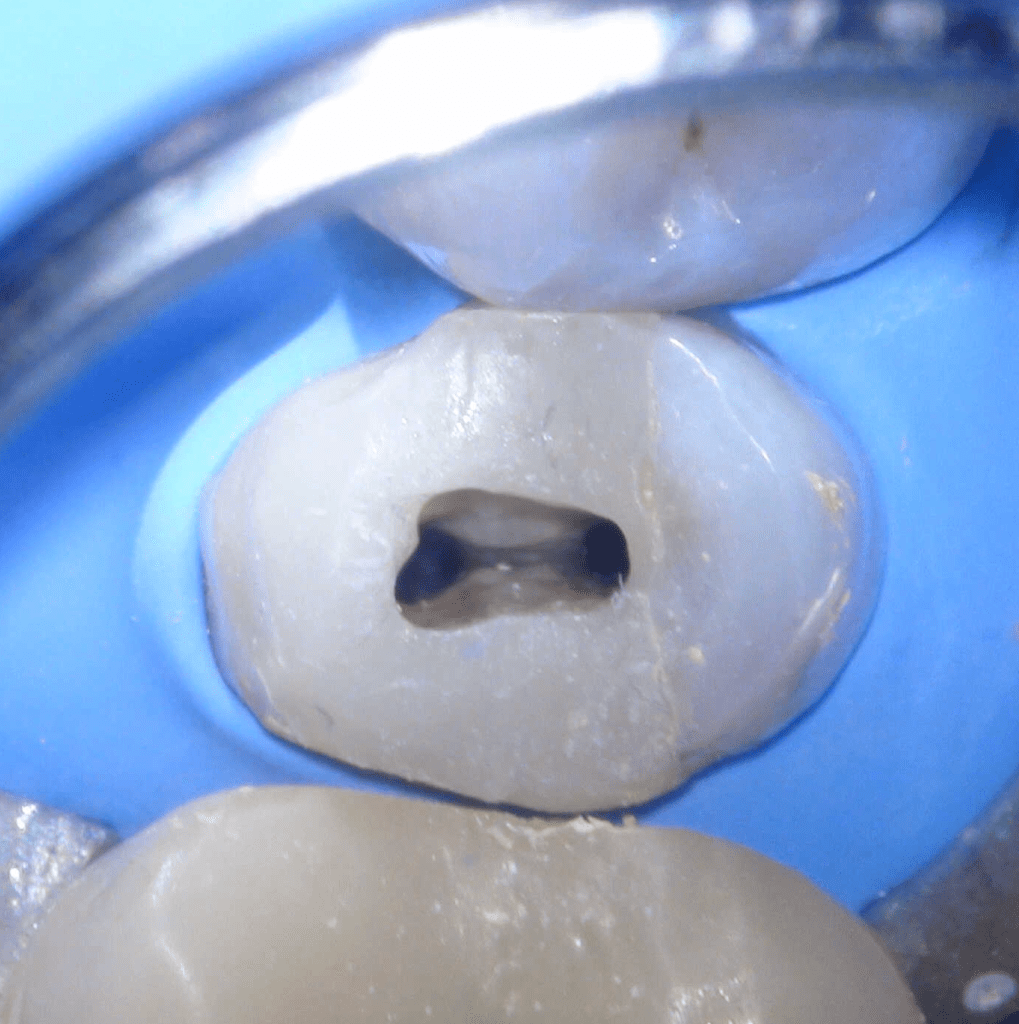

Pulpotomía biodentine + reco preendio